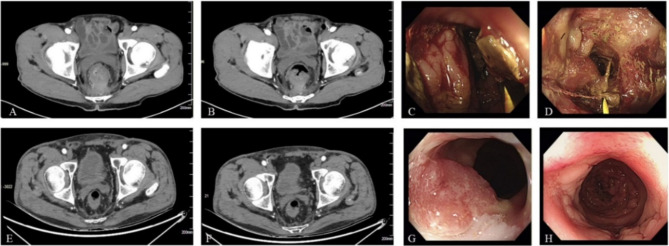

Necrotizing fasciitis (NF) is a rare and life-threatening serious infectious disease, characterized by acute onset and rapid progress, leading to extensive necrosis of skin, soft tissue as well as fascia by a variety of aerobic and anaerobic bacteria, localized on external genitalia, scrotum, groin and perianal areas in males. There exist numerous common etiologies for NF, yet NF induced by malignant neoplasms is exceedingly rare. Several studies have reported that NF may be associated with tumor site (rectal/sigmoid colon cancer) and blood supply dysfunction caused by targeted therapy drugs (bevacizumab, aflibercept, ramucirumab). The perforation of colorectal cancer poses a unique risk factor for NF. However, in our two cases, the patient with rectal cancer received CapeOX (oxaliplatin + capecitabine) + bevacizumab + tislelizumab for 3 cycles without perforation but did develop NF. One month after debridement, the patient continued immunotherapy with tislelizumab alone for the fourth cycle and maintained for an additional 3 cycles without any recurrence of NF. Therefore, does the occurrence of NF correlate with the tumor site (rectum) and targeted immunotherapy? Another patient with hepatocellular carcinoma also developed NF after receiving 2 cycles of lenvatinib + sintilimab treatment. The third cycle of sintilimab immunotherapy was administered on the 13th day after operation, which was subsequently maintained for an additional 2 cycles without recurrence of NF. The absence of a direct correlation between hepatocellular carcinoma and rectal tumor location as well as immunotherapy, suggests that NF may be closely linked to targeted therapy.